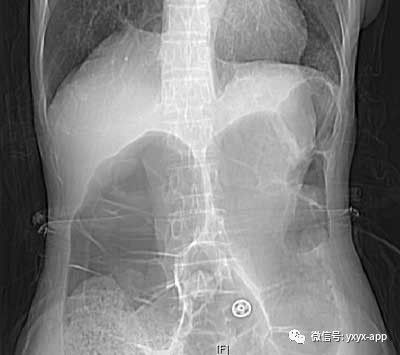

Gut:一例乙状结肠扭转的案例报道| 消化客_

1028x798 - 104KB - JPEG